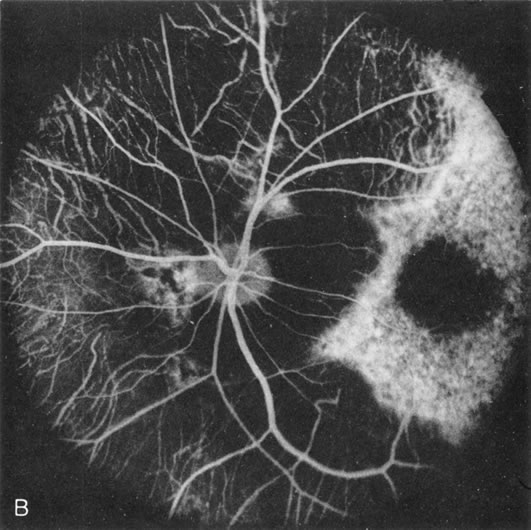

Generalized choroidal dystrophy is usually noted in middle-aged mildly symptomatic individuals who show a predominantly peripapillary or pericentral distribution of choroidal atrophy. Gradually, over the years these areas enlarge to eventually involve the entire retina. These changes are vividly seen on FA (Fig. 6).

Fig. 6. Generalized choroidal dystrophy. This 65-year-old woman gradually developed enlarging, progressive areas of choroidal atrophy over a 20-year period. When initially seen, the abnormalities were confined to the peripapillary and macular region (A,B). In a recent examination, the generalized choroidal atrophy is vividly demonstrated on angiography (C–F).